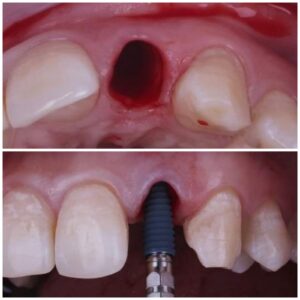

جماليات زراعة الأسنان

يتم تخطيط وتنفيذ إجراء زراعة الأسنان بعناية لضمان أن ترميم الأسنان يبدو طبيعيًا في الشكل واللون والمكان. نعطي الأولوية لراحة مرضانا بالإضافة إلى الجماليات. وهذا يتطلب مزيجًا مثاليًا من العبقرية الفنية والجراحية. لذلك ، يتم تنفيذ جميع حالات الزرع لدينا من قبل فريق من أطباء الأسنان التجميليين وأخصائي زراعة الأسنان.